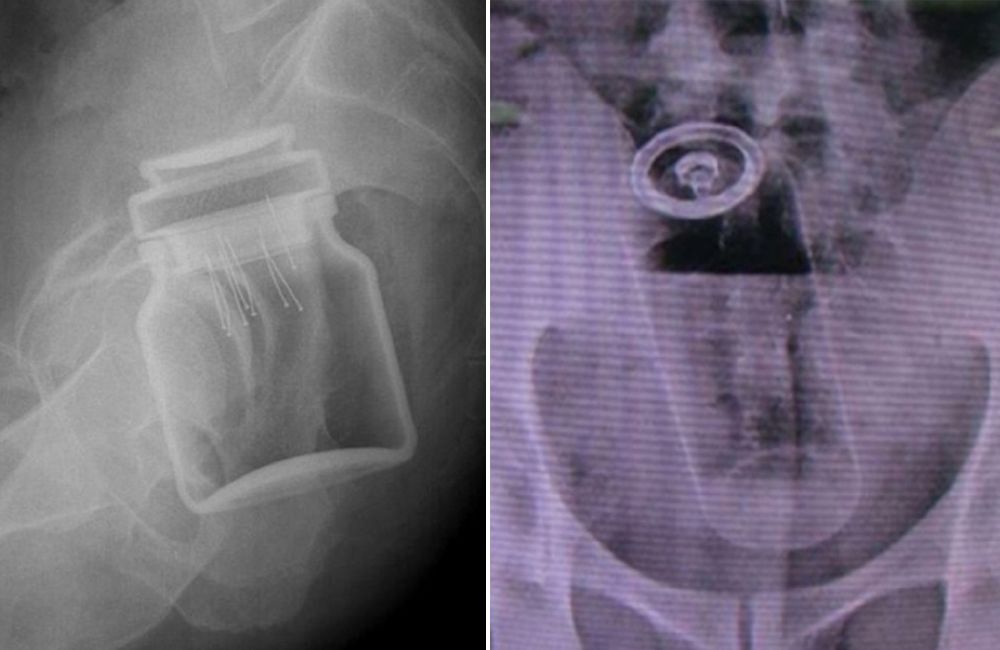

Odkryli tajemniczą skrzynkę na dnie Bałtyku. Oto, co było w środku